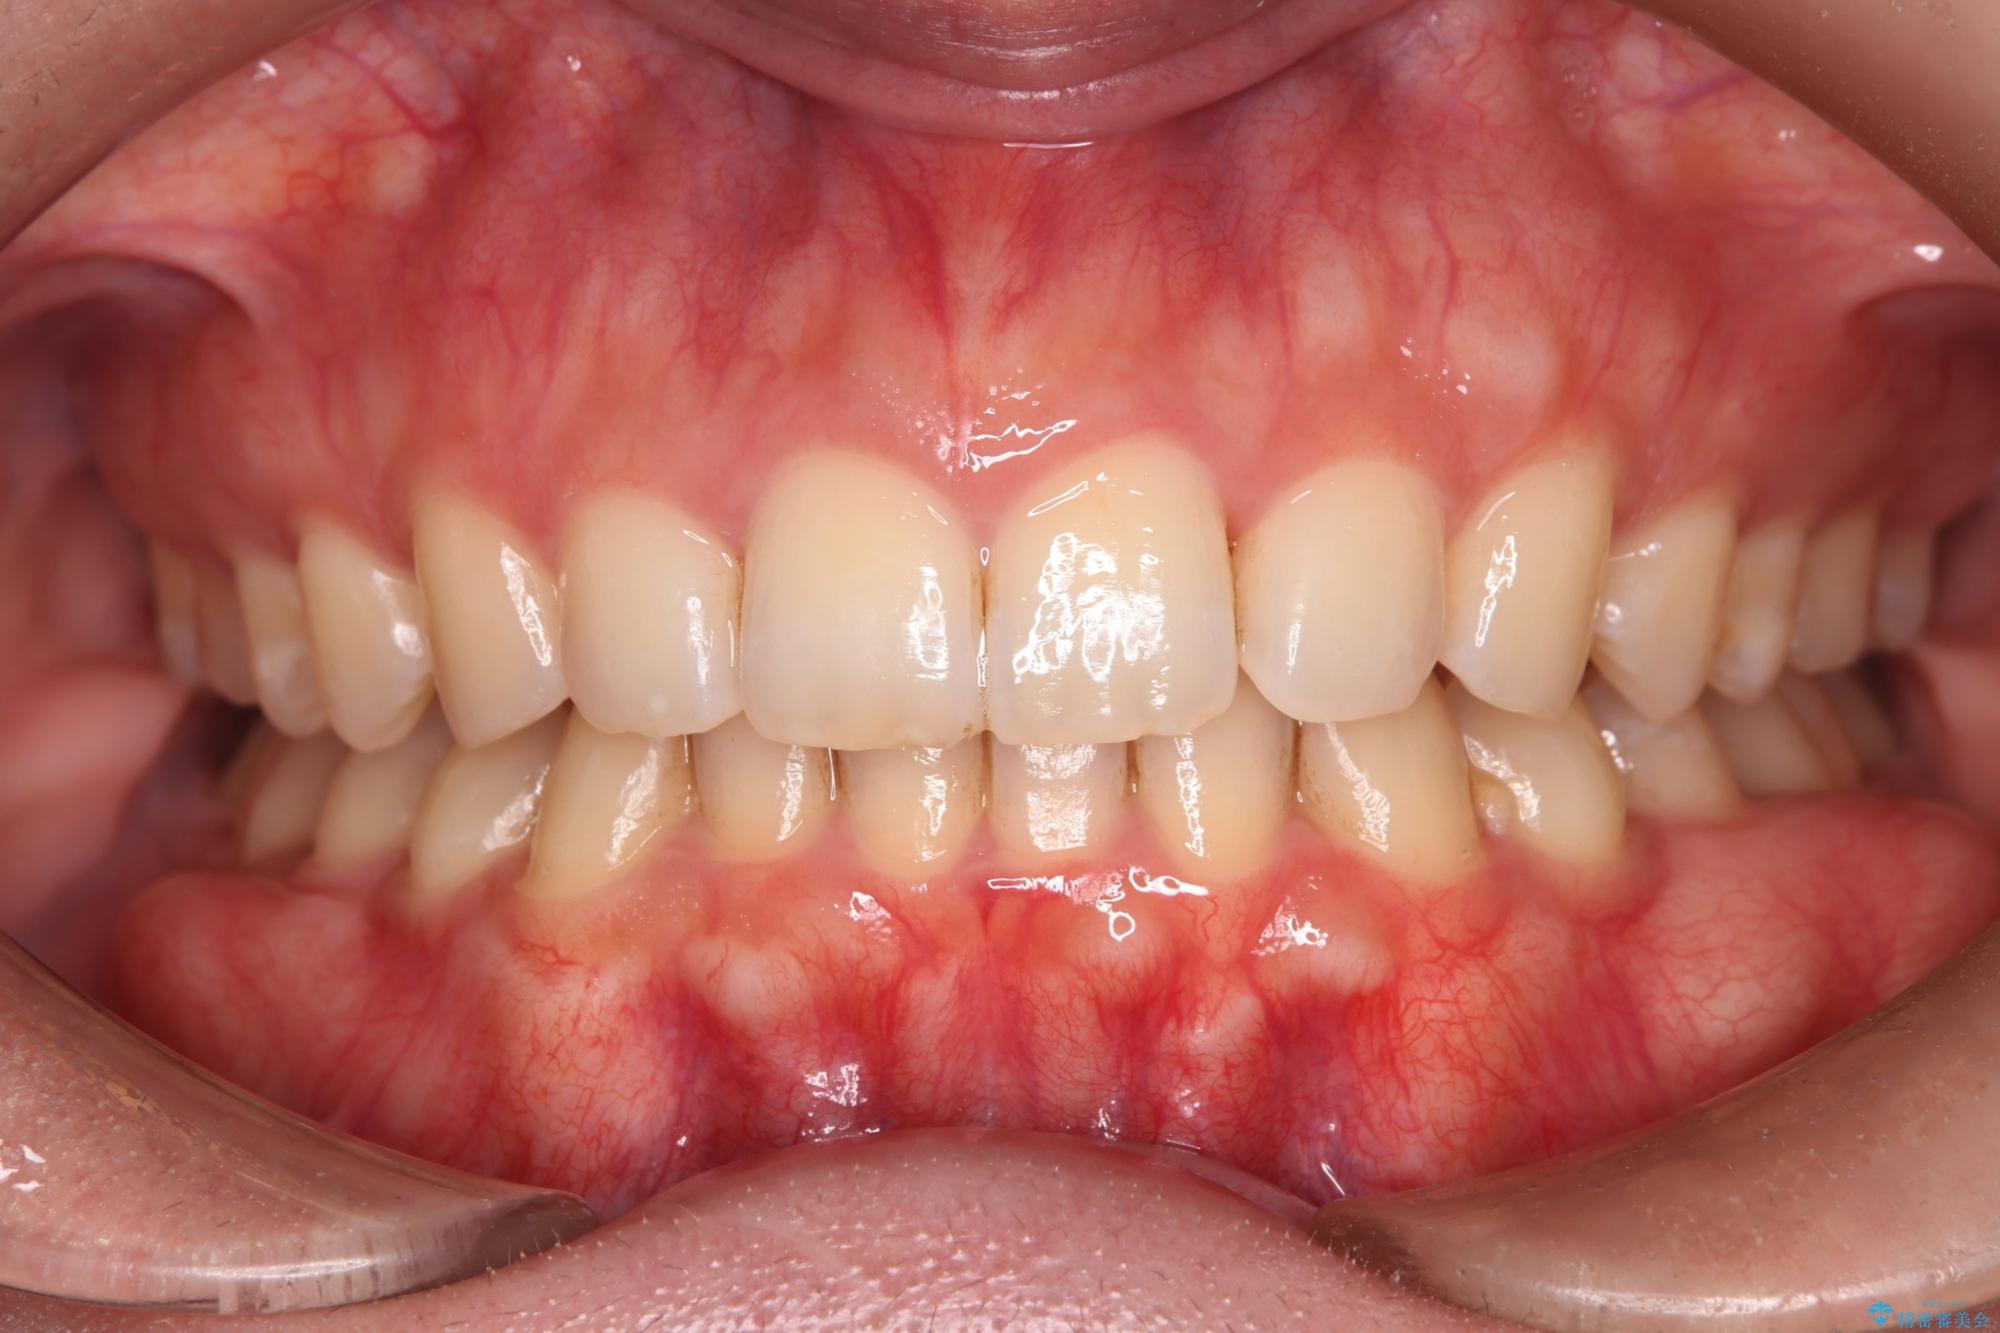

治療後について

噛み合わせをよくするために、ワイヤー矯正とインビザライン矯正のどちらの期間も必要な箇所にゴム掛けを行いながら治療を行いました。

ゴム掛けを頑張っていただいたので、噛みあわせも改善され綺麗な歯並びになりました。